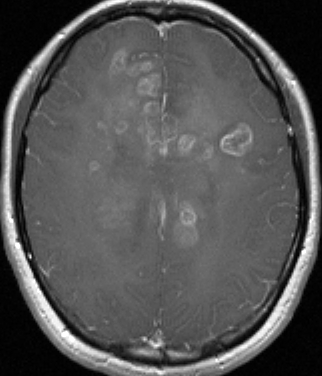

若い成人です,認知機能障害で発症しました。この画像を見るからに悪性神経膠腫,少なくともグレード3のグリオーマであることは明白です。しかし,グレード4膠芽腫あるいはグレード3退形成性星細胞腫にしては腫瘍周辺浮腫が軽すぎます。ですから,グレード3の退形成性乏突起膠腫 AO かも。認知機能の回復と温存を考量して,脳梁損傷と前交連損傷を避けて,右上前頭回と帯状回腫瘍を摘出しました。

左は術後のT1強調ガドリニウム増強像で,残存腫瘍がわかります。この腫瘍に対してICE (IFO/CDDP/VP-16) 化学療法を1コースしました。右側のMRIが1ヶ月後の画像です。このように1p/19q欠失のある退形成性乏突起膠腫は,化学療法感受性がとても高い悪性グリオーマです。ですから,手術で後遺症を残さないように,勢い込んで腫瘍を摘出しようとしないことが大切です。光顕診断はAOで,後々の解析で1p/19q codeletion でした。